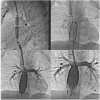

The Fontan operation represents the last of multiple steps that are offered a wide range of congenital cardiac lesions with a single ventricle (SV) physiology. Nowadays this surgical program consists of a total cavopulmonary connection (TCPC), by anastomosing systemic veins to the pulmonary arteries (PAs), excluding the right-sided circulation from the heart. As a result of imaging, surgical, percutaneous, and critical care improvements, survival in this population has steadily increased. However, the Fontan physiology chronically increases systemic venous pressure causing systemic venous congestion and decreased cardiac output, exposing patients to the failure of the Fontan circulation (FC), which is associated with a wide variety of clinical complications such as liver disease, cyanosis, thromboembolism, protein-losing enteropathy (PLE), plastic bronchitis (PB), and renal dysfunction, ultimately resulting in an increased risk of exercise intolerance, arrhythmias, and premature death. The pathophysiology of the failing Fontan is complex and multifactorial; i.e., caused by the single ventricle dysfunction (diastolic/systolic failure, arrhythmias, AV valve regurgitation, etc.) or caused by the specific circulation (conduits, pulmonary vessels, etc.). The treatment is still challenging and may include multiple options and tools. Among the possible options, today, interventional catheterization is a reliable option, through which different procedures can target various failing elements of the FC. In this review, we aim to provide an overview of indications, techniques, and results of transcatheter options to treat cavopulmonary stenosis, collaterals, impaired lymphatic drainage, and the management of the fenestration, as well as to explore the recent advancements and clinical applications of transcatheter cavopulmonary connections, percutaneous valvular treatments, and to discuss the future perspectives of percutaneous therapies in the Fontan population.